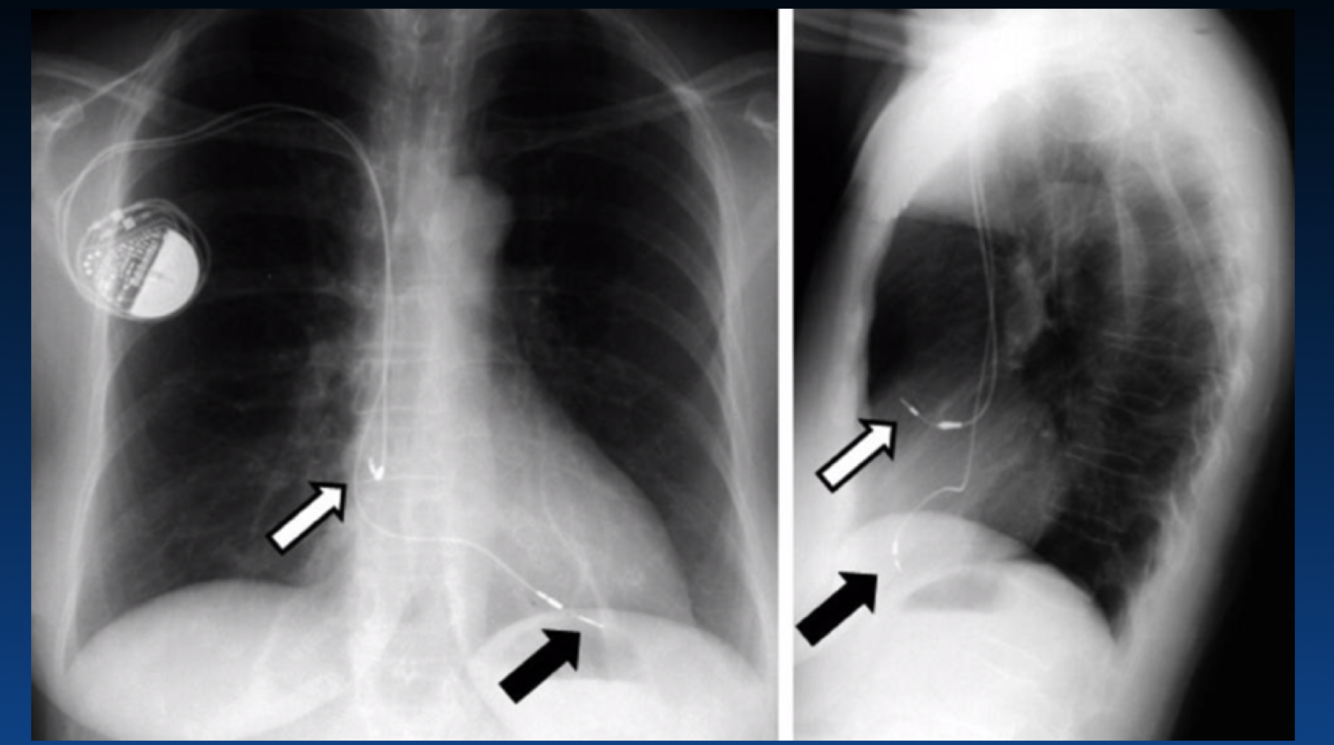

Name the Pacemaker/ICD Complication

What is wrong with this?

Misplaced lead

What is Twiddler Syndrome?